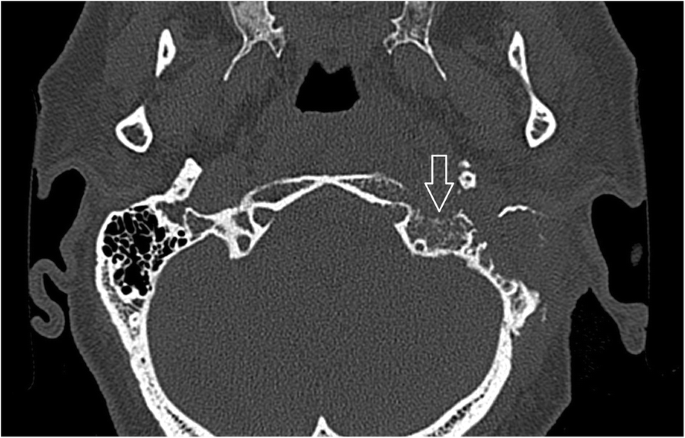

Sreepada et al. consider the tympanomastoid suture crucial for spread of infection [14]. The swelling of soft tissues adjacent to the tympanomastoid and petrotympanic sutures and stylomastoid foramen was visible in all cases on non-contrast CT scans. Therefore the authors consider it as a warning sign suggestive of further progression of skull base infection, similarly as reported in malignant otitis externa [15]. Sreepada also recommends CT follow-up for CSBO even though the osteolytic changes of the compact bone on CT represents a rather late sign, as 30% of bone must be demineralized to appear eroded on CT scans (Fig. 11). If soft tissue changes were visible on non-contrast enhanced CT scans, the suspicion of inflammation was raised. MRI is considered essential for CSBO diagnosis [16]. Venous channels and fascial planes facilitate the spread along the dural venous sinuses. Two experienced radiologists were asked to trace the infection spread on CT and MRI scans. After acquisition of the data, the pathways can be traced even by post-processing imaging methods [7]. Hence, most active disease was found in the compact bone along the middle and posterior cranial fossa surfaces with extension to the petrous apex [14]. In patient No 2 the infection also involved the temporomandibular joint and parotid gland and the upper eyelid on the affected side. This was due to an anatomical variant, persistent foramen of Huschke, which allowed infection spread from the external auditory canal to the temporomandibular joint [17]. In this region, advanced diffusion imaging MRI can be used [18]. The rudimentary foramen was also observed in one case and facilitated infection spread towards the temporomandibular joint and surrounding tissues.

Patient No: 3, five months following mastoidectomy and antibiotic treatment: amoxicillin/clavulanic acid, gentamycin, clarithromycin and dalacin. Non-enhanced CT image (bone window) axial scan cross section of temporal and occipital bones. Osteolysis of the compact bone in the left lateral skull base represents a late sign of osteomyelitis (arrow). Minor changes of spongy bone and major changes of compact bone highlight spread of infection under the periosteum, but represents a late sign of the infection